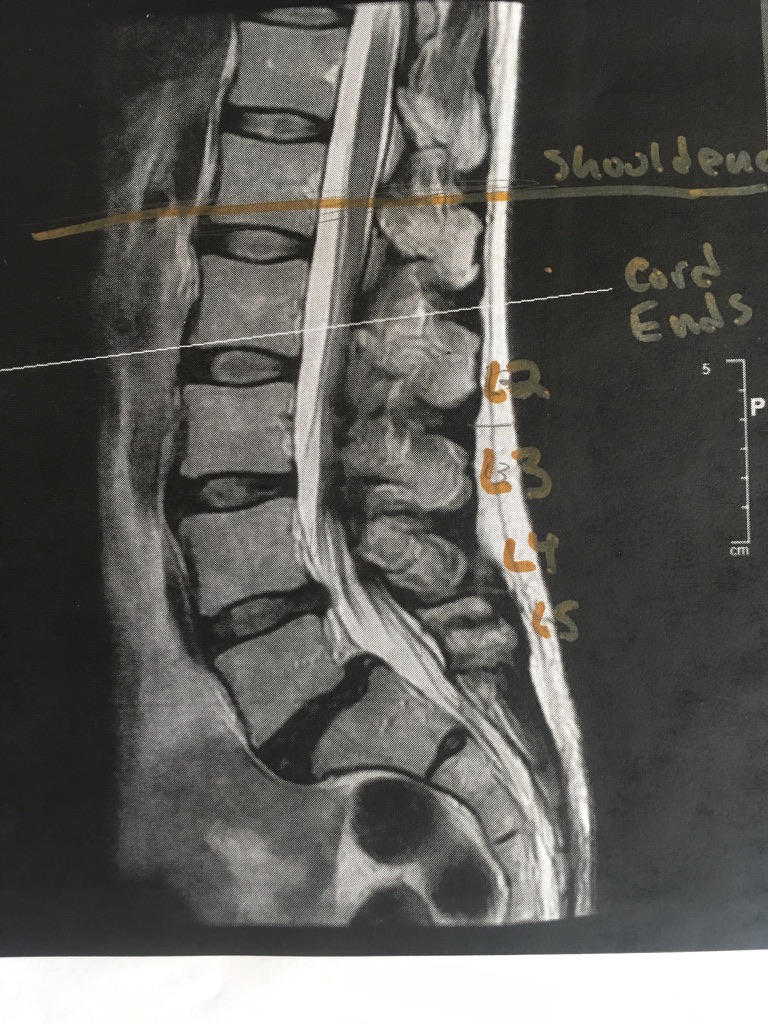

Here Dr. Klinge showed me where normal spinal cords should terminate at the bottom, and where mine ends. (Mine ends lower, because it’s tethered.)